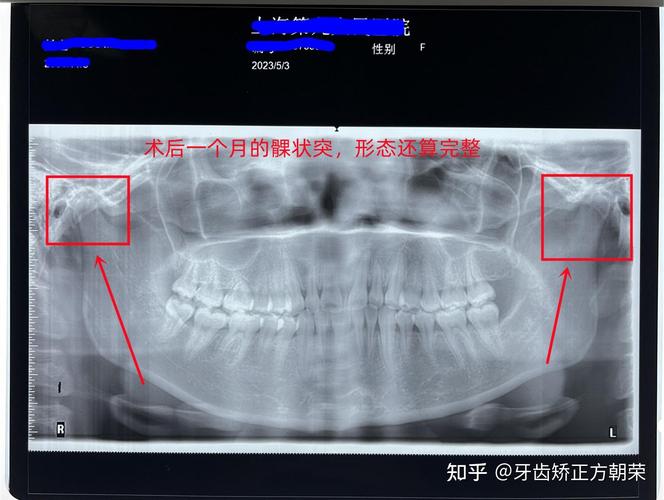

下颌骨全景片(曲面断层片,Orthopantomogram, OPG)

- 原理: 患者站立或坐着,下颌置于旋转架的托板上,X线管和探测器(胶片或数字探测器)围绕患者头颅做同步旋转,获得下颌骨、上下颌牙列及部分颞下颌关节的连续、全景影像。

- 观察整个下颌骨(体部、升支、髁突、喙突)的整体形态、连续性。

- 观察颞下颌关节的大致位置和形态(但不如专用关节片清晰)。

- 存在影像变形、放大和重叠(尤其是升支后部和髁突区域)。